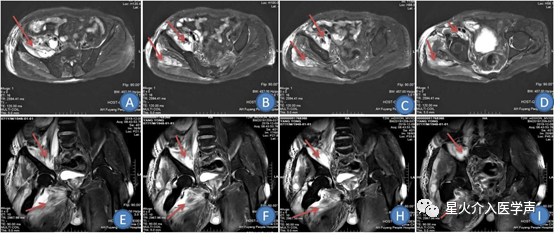

入院后完善相关检查,在数字减影血管造影下行盆腔脓肿穿刺引流术,术前阅读盆腔CT定位右侧盆腔脓肿大致解剖位置,于右侧髂前上棘下方2cm平腰4椎体水平与为穿刺点,局麻后穿刺脓肿成功,经穿刺针注入造影剂造影示:[2] 右侧髂窝见一巨大脓腔,大小约10cm×5cm×4cm(图6),未见脓液累及股管。术中置入引流管,引流管外接引流袋。术后常规穿刺脓液常规细菌培养及药敏试验选择敏感抗生素、脓腔定期冲洗、保持负压引流管通畅等对症支持治疗。一周后右腹股沟出现一6cm×4cm大小溃疡面,基底部红。急查血常规:白细胞计数20.06×109/L,中性粒细胞比80.9%。盆腔部CT:右侧盆腔脓肿仍有,引流管在位(图3,4)及盆腔MRI:右侧髂腰肌、腰大肌及股臀部软组织脓肿形成(图A-I)[岁3] 。结合患者盆腔脓肿引流欠佳,遂再次行脓肿穿刺引流术,术中经原引流管造影示:右侧盆腔脓肿与右侧股脓腔经股管相通(图6,7),术中经股管置入6F引流管,引流管远端送至右侧股脓肿脓腔远端,术后股脓肿引流管外接负压引流球及引流袋组合装置(山东贝诺斯医疗器械,图5)。所引流脓液行细菌培养和药敏试验,根据脓液药敏结果选择敏感抗生素抗感染。[岁4] 每日先用250 mL生理盐水经引流管反复冲洗股脓肿及回抽脓腔液至体外,直至回抽纵液体清亮时结束。再注入25mL庆大霉素与生理盐水混合液冲洗脓腔,保留30分钟后连接负压球持续引流。每间隔4-6天复查盆腔CT观察脓腔面积缩小程度及引流管远端位置,必要时在DSA下逐步外撤调整引流管位置,保持引流管末端位于尚未闭锁的脓腔下极为最佳[1]。患者15天复查盆腔部CT:股脓肿明显吸收,透视下将引流管拔出至体外,三月后门诊随访患者恢复良好。

图A-D为右侧髂肌及腰大肌及股臀部软组织脓肿MR T2加权轴位动态图像(脓肿为箭头所指);图E-I为右侧髂肌及腰大肌及股臀部软组织脓肿MR T2加权冠状位动态图像(脓肿为箭头所指)